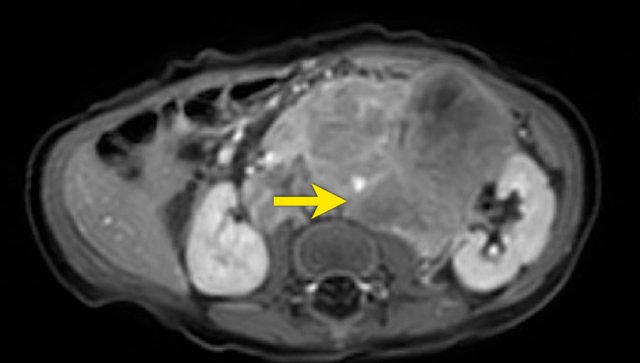

This is an axial gadolinium enhanced T1W-image with fat suppression.

It shows the encasement of the vessels.

Notice the tumor extension posterior to the aorta, which is displaced away from the vertebral column (arrow).